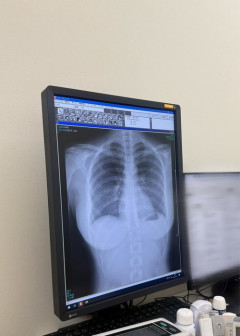

【画像】グラドルさん、セクシーすぎるレントゲン写真を公開するwwww

1: 2026/01/24(土) 11:03:00.30 22歳グラドル「肺綺麗でした」 まさかの部位を捉えたレントゲン写真が話題「曲線美」 肺綺麗でした pic.twitter.com/oprlolFN39— 豊島 心桜 (@CocoroToyoshima) January 23, 2026 ※関連記事 【画像】わき毛を剃らないグラドルさん、『年忘れわき毛』を公開して勇気を称えられるwwwww…

【画像】まんさん、健康診断のレントゲン検査で肺が綺麗なことアピールした結果